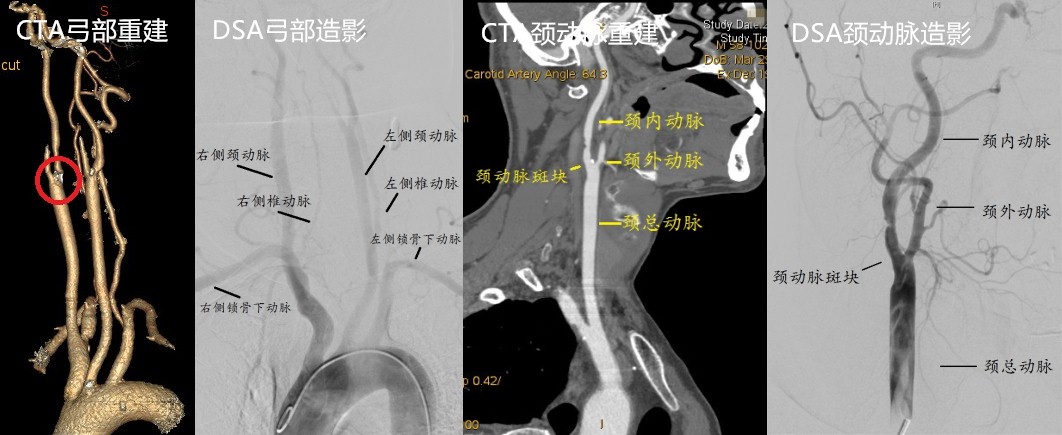

李伯伯今年61岁,吸烟40余年,发现高血压2余年,最高185/85mmHg,一直未规律服药。退休之后本想享享清福,没承想3个月来一直头晕乏力,偶尔还有眼前发黑视物不清。就诊清华长庚医院血管外科门诊,检查发现右侧颈动脉粥样硬化斑块形成、重度狭窄,超声造影检查及颈动脉斑块MRI分析均提示不稳定斑块,极易破碎脱落导致脑梗死。血管外科团队为李伯伯行颈动脉内膜剥脱术,术后症状明显缓解,恢复5天后顺利出院。

颈动脉彩超检查能够做出初步判断,但其受检查技师操作经验及主观判断影响大。为了进一步指导手术治疗,还需要明确颈动脉狭窄部位、长度以及程度、斑块成分等详细信息。颈动脉血管造影(DSA)能准确检查出动脉狭窄的程度和范围,是诊断动脉病变的金标准。近年来,应用超声造影技术、CT血管增强(CTA)以及磁共振血管成像(MRA)技术,同样可以得到全面的动脉狭窄信息,通过三维建模从不同的角度显示血管结构,良好地识别不稳定斑块。